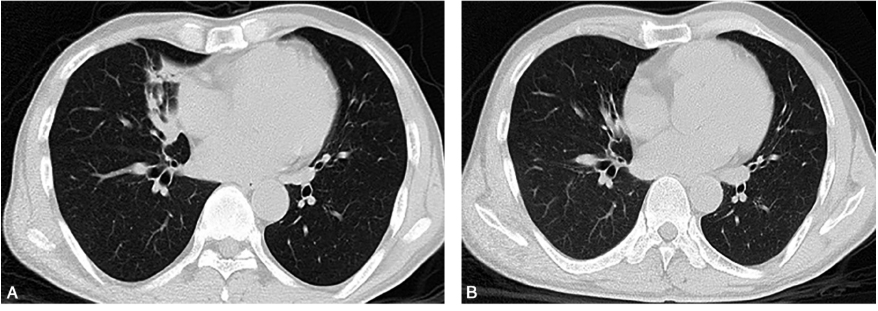

患者予青霉素治疗2天后,患者咳嗽、咳痰症状好转,体温恢复正常。治疗一周后血培养未生长细菌;血常规:白细胞:12.32×109/L,中性粒细胞:79%。查体:双肺呼吸音稍粗,未闻及干、湿性啰音。3个月后复查胸部CT:右肺中叶高密度影已基本吸收,右上肺结节明显吸收变小(图3)。

图3 胸部CT随访:青霉素治疗后3个月胸部CT(B)显示较治疗前(A)病灶已基本吸收消散